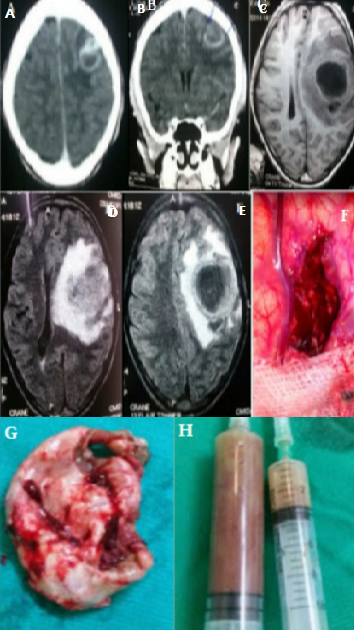

The cerebral abscess represents 2% of the intracranial lesions of the adult, 17% of the child. 35% of abscesses develop before the age of 15 years. It evolves in several phases (pre-suppurative encephalitis, purulent collection without shell, abscess collected with fine capsule, abscess collected with thick shell). We report the case of a 14-year-old girl with no specific pathological history except a neglected oral infection episode; has been present for 4 weeks with headache, vomiting, tonic-clonic convulsive seizures in a febrile context. On examination there is a proportional right hemiparesis with a motor force rated at 3/5 without facial participation, a fever at 39.5°c. The biological examination revealed a leucocytosis (17 000/mm3) predominantly neutrophilic (81%). The brain CT Scan with injection of iodinated contrast medium in axial (A) and coronal (B) sections revealed an isodense occupying process, with a left parietal seat, with annular rehabitation and partitioned, measuring 23.8mm x 20mm and presenting an edema in the satellite. Brain MRI was found 3 weeks later in sequences, T1 (C), T2 Flair (D, E), T1 gado in axial section a volumetric increase of the occupying process with a significant deviation from the line of the median structures. A craniotomy with evacuation of the abscess (F, H) and excision of the cyst wall (G) was performed. The bacteriological examination of the pus was negative. Anatomopathological examination of the cyst wall revealed non-specific inflammatory necrotic tissue. An intravenous antibiotherapy was established in post-operative stages, the clinical course proved to be significantly favorable.